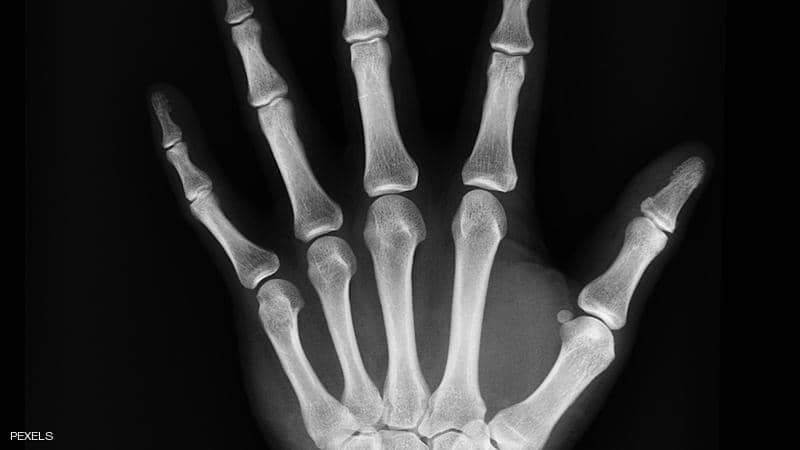

7 نصائح.. كيف تحمي عظامك مع تقدمك في العمر

يقول العلم إنه كلما تقدم الإنسان في العمر، أصبحت عظامه أكثر رقة وأقل كثافة، الأمر الذي يجعلها عرضة لأمراض عدة، وهو ما يتطلب عناية خاصة تحميها من الكسر.

يمكن للأطباء الحصول على صورة أشعة سريعة للتأكد من أن كثافة العظام سليمة. ويساعد هذا الفحص في تحديد مخاطر الإصابة بمرض هشاشة العظام والكسور.